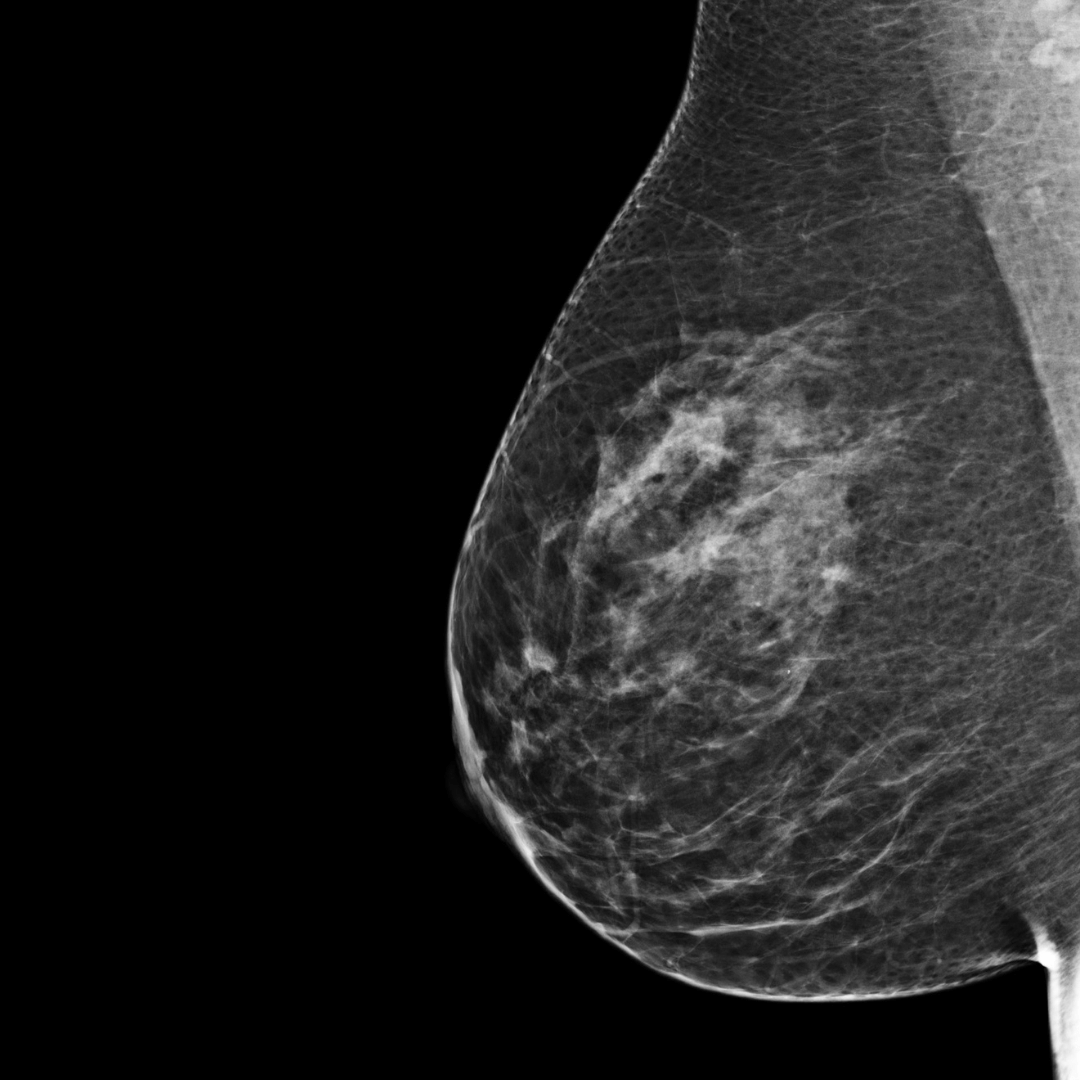

Category B

BI-RADS category B:

There are scattered areas of fibroglandular density. The breast tissue is not dense.